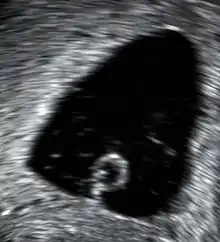

Aborto espontâneo ou interrupção involuntária da gravidez (IIG) é a morte natural do embrião ou feto antes de este ter a capacidade de sobreviver fora do útero.[1][3] Algumas recomendações determinam um limite de 20 semanas de gestação, sendo a partir desse momento designado nado-morto.[11] O sintoma mais comum de um aborto espontâneo é hemorragia vaginal com ou sem dor.[1] É comum que a mulher sinta tristeza, ansiedade e culpa.[2][12] O corpo pode expelir tecidos e material coagulado pelo canal vaginal.[13] Quando a mulher tem sucessivos abortos espontâneos, está-se na presença de infertilidade.[14]

| Método de diagnóstico | Exame, gonadotrofina coriónica humana, ecografia[8] |

Entre os fatores de risco para um aborto espontâneo estão a gravidez em idade avançada, ter antecedentes de aborto, a exposição ao fumo de tabaco, obesidade, diabetes, problemas de tiroide e consumo de drogas ou álcool.[5][6] Cerca de 80% dos abortos espontâneos ocorrem durante as primeiras 12 semanas de gravidez, ou primeiro trimestre.[1] Em cerca de metade dos casos, a causa subjacente envolve anomalias cromossómicas.[4][1] O diagnóstico de um aborto espontâneo consiste geralmente num exame para verificar se o colo do útero se encontra aberto ou encerrado, análises ao sangue para avaliar os níveis de gonadotrofina coriónica humana e uma ecografia.[8] Entre outras condições que podem manifestar sintomas semelhantes estão uma gravidez ectópica e hemorragia de nidação.[1]